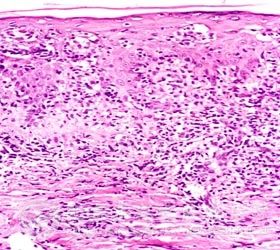

蕈样肉芽肿的病理改变有哪些呢?北京京城皮肤医院介绍,蕈样肉芽肿的重要病理改变和一般病理改变有以下几种:

重要病理改变:

1、处于斑片期患者的病理变化表现为表皮内出现单个散在分布或聚集成团的异型淋巴*。

2、处于肿瘤期的患者表现为 内有成团或弥漫性的异型淋巴*浸润,常累及皮下组织。

一般的病理改变

1、一般来说红斑期的组织病理缺乏特异性的改变。处于斑片期的患者病理表现为 乳头层的毛细血管周围灶性淋巴样*浸润,并且常向表皮内外移,单个散在分布或者聚集成团。

2、处于晚期浸润斑块和肿瘤期的患者,其病理表现为整个 甚至皮下组织内有成团或弥漫性浸润蕈样肉芽肿*,比正常的淋巴*大、染色深,胞核扭曲、畸形,核膜呈不规则凹陷

3、*检查时的变化:蕈样肉芽肿*在进行CD5、CD3、CD4、CD8和HLA-DR*检查时的均呈阳性反应。